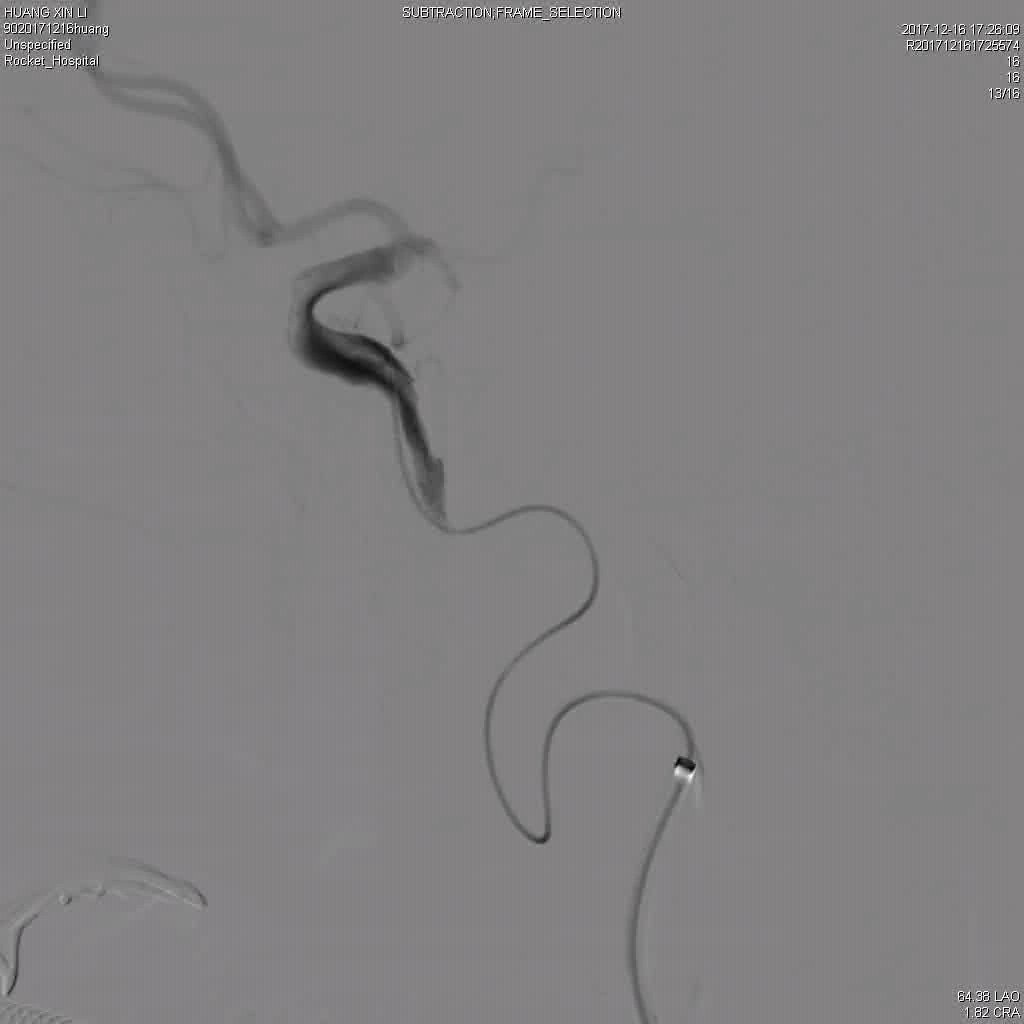

DSA显示ICAO

微导管造影证实MCAO

手术过程

中间导管配合在长鞘和小球囊的配合下穿过迂曲夹层的颈内动脉。

微导管微导丝越过MCA闭塞段,置入取栓支架支架。